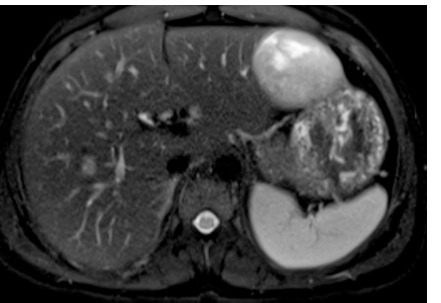

Glycogen Storage Disease Type 1b (GSD Type 1b) is predominantly diagnosed in childhood. Rare cases emerging in adulthood present a unique set of clinical challenges, particularly concerning liver lesions. We report a 22-year-old male diagnosed unusually late with GSD Type 1b, underlining the hepatic complexities involved. He initially presented with hepatomegaly and solid nodular lesions in the liver. An abdominal magnetic resonance imaging (MRI) revealed a sizable hepatocellular adenoma (HCA), subsequently removed through surgical segmentectomy. Histopathology confirmed the lesion as a hepatocyte nuclear factor-1 alpha (HNF-1alpha) mutation-positive HCA. Follow-up MRI revealed the persistence of multiple smaller liver nodules, necessitating continued clinical surveillance. Hepatic adenomas are a common complication in GSD Type 1 patients, posing management challenges due to their size, multiplicity, and risk of malignancy. While liver transplantation is a last resort option, it can worsen metabolic control. Sodium-glucose cotransporter-2 (SGLT-2) inhibitors offer a potential alternative for improving glycemic regulation and possibly affecting the adenoma size.